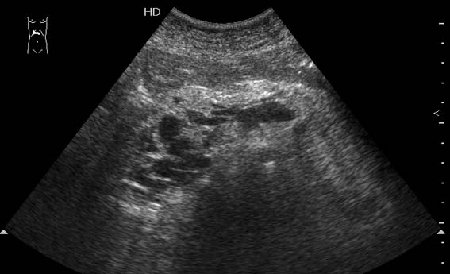

Тромбоз верхней брыжеечной вены

Женщина средних лет, клинический диагноз при поступлении - хронический панкреатит

Да, действительно, формирование варикоза в области головки панкреас характерно для тромбоза верхней брыжеечной вены.Брехт писал(а):Верхней брыжеечной

Ургентность здесь относительная, это неострый тромбоз - для развития коллатералей необходимо время. В хирургической клинике при хроническом панкреатите мы нередко видим тромбозы воротной вены, селезеностой вены. Но тромбоз ВБВ встречается нечасто и заподозрить его можно по "гроздьям" варикозов в области головки панкреас. На пилетромбоз обычно указвают "гроздья" варикозов в воротах печени.besliu писал(а):Спасибо за случай,впервые вижу такую патологию,ургентность в поликлинике не так уж частая![]()